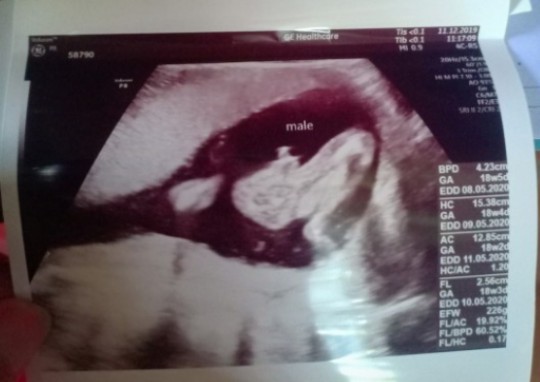

เห็นเพศตอน16w น้องเป็นผช

20 wk เห็นเลยคะว่ามีจู๋